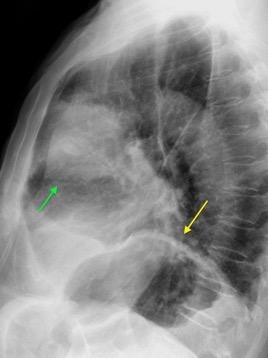

Tromboembolismo pulmonar Diafragma elevado 20%

Nódulos pulmonares múltiples. (flechas verdes). Masas paratraqueales. (flechas amarillas). Dudoso ensanchamiento retrocrural (flechas negras). sigue….

T. mixto de células germinales del testículo

izquierdo Metástasis pulmonares. (flechas verdes). Ganglios paratraqueales. (flechas amarillas). Ganglios retroperitoneales (flechas negras)